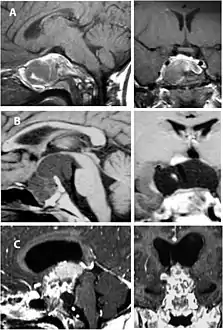

Imaging scans for craniopharyngioma

A physician can conduct a few scans and tests to diagnose a person with craniopharyngioma.[19] High-resolution magnetic resonance imaging (MRI) is commonly used as a diagnostic tool; however, computer tomography (CT) remains the gold standard imaging choice for craniopharyngioma diagnosis as it can detect the severity of the calcification within the tumour.[20]

In some cases, a powerful 3T (Tesla) MRI scanner can help define the location of critical brain structures affected by the tumor. The histologic pattern consists of nesting of squamous epithelium bordered by radially arranged cells. It is frequently accompanied by calcium deposition and may have a microscopic papillary architecture. A computed tomography (CT) scan is also a good diagnostic tool, as it detects calcification in the tumor.[21]